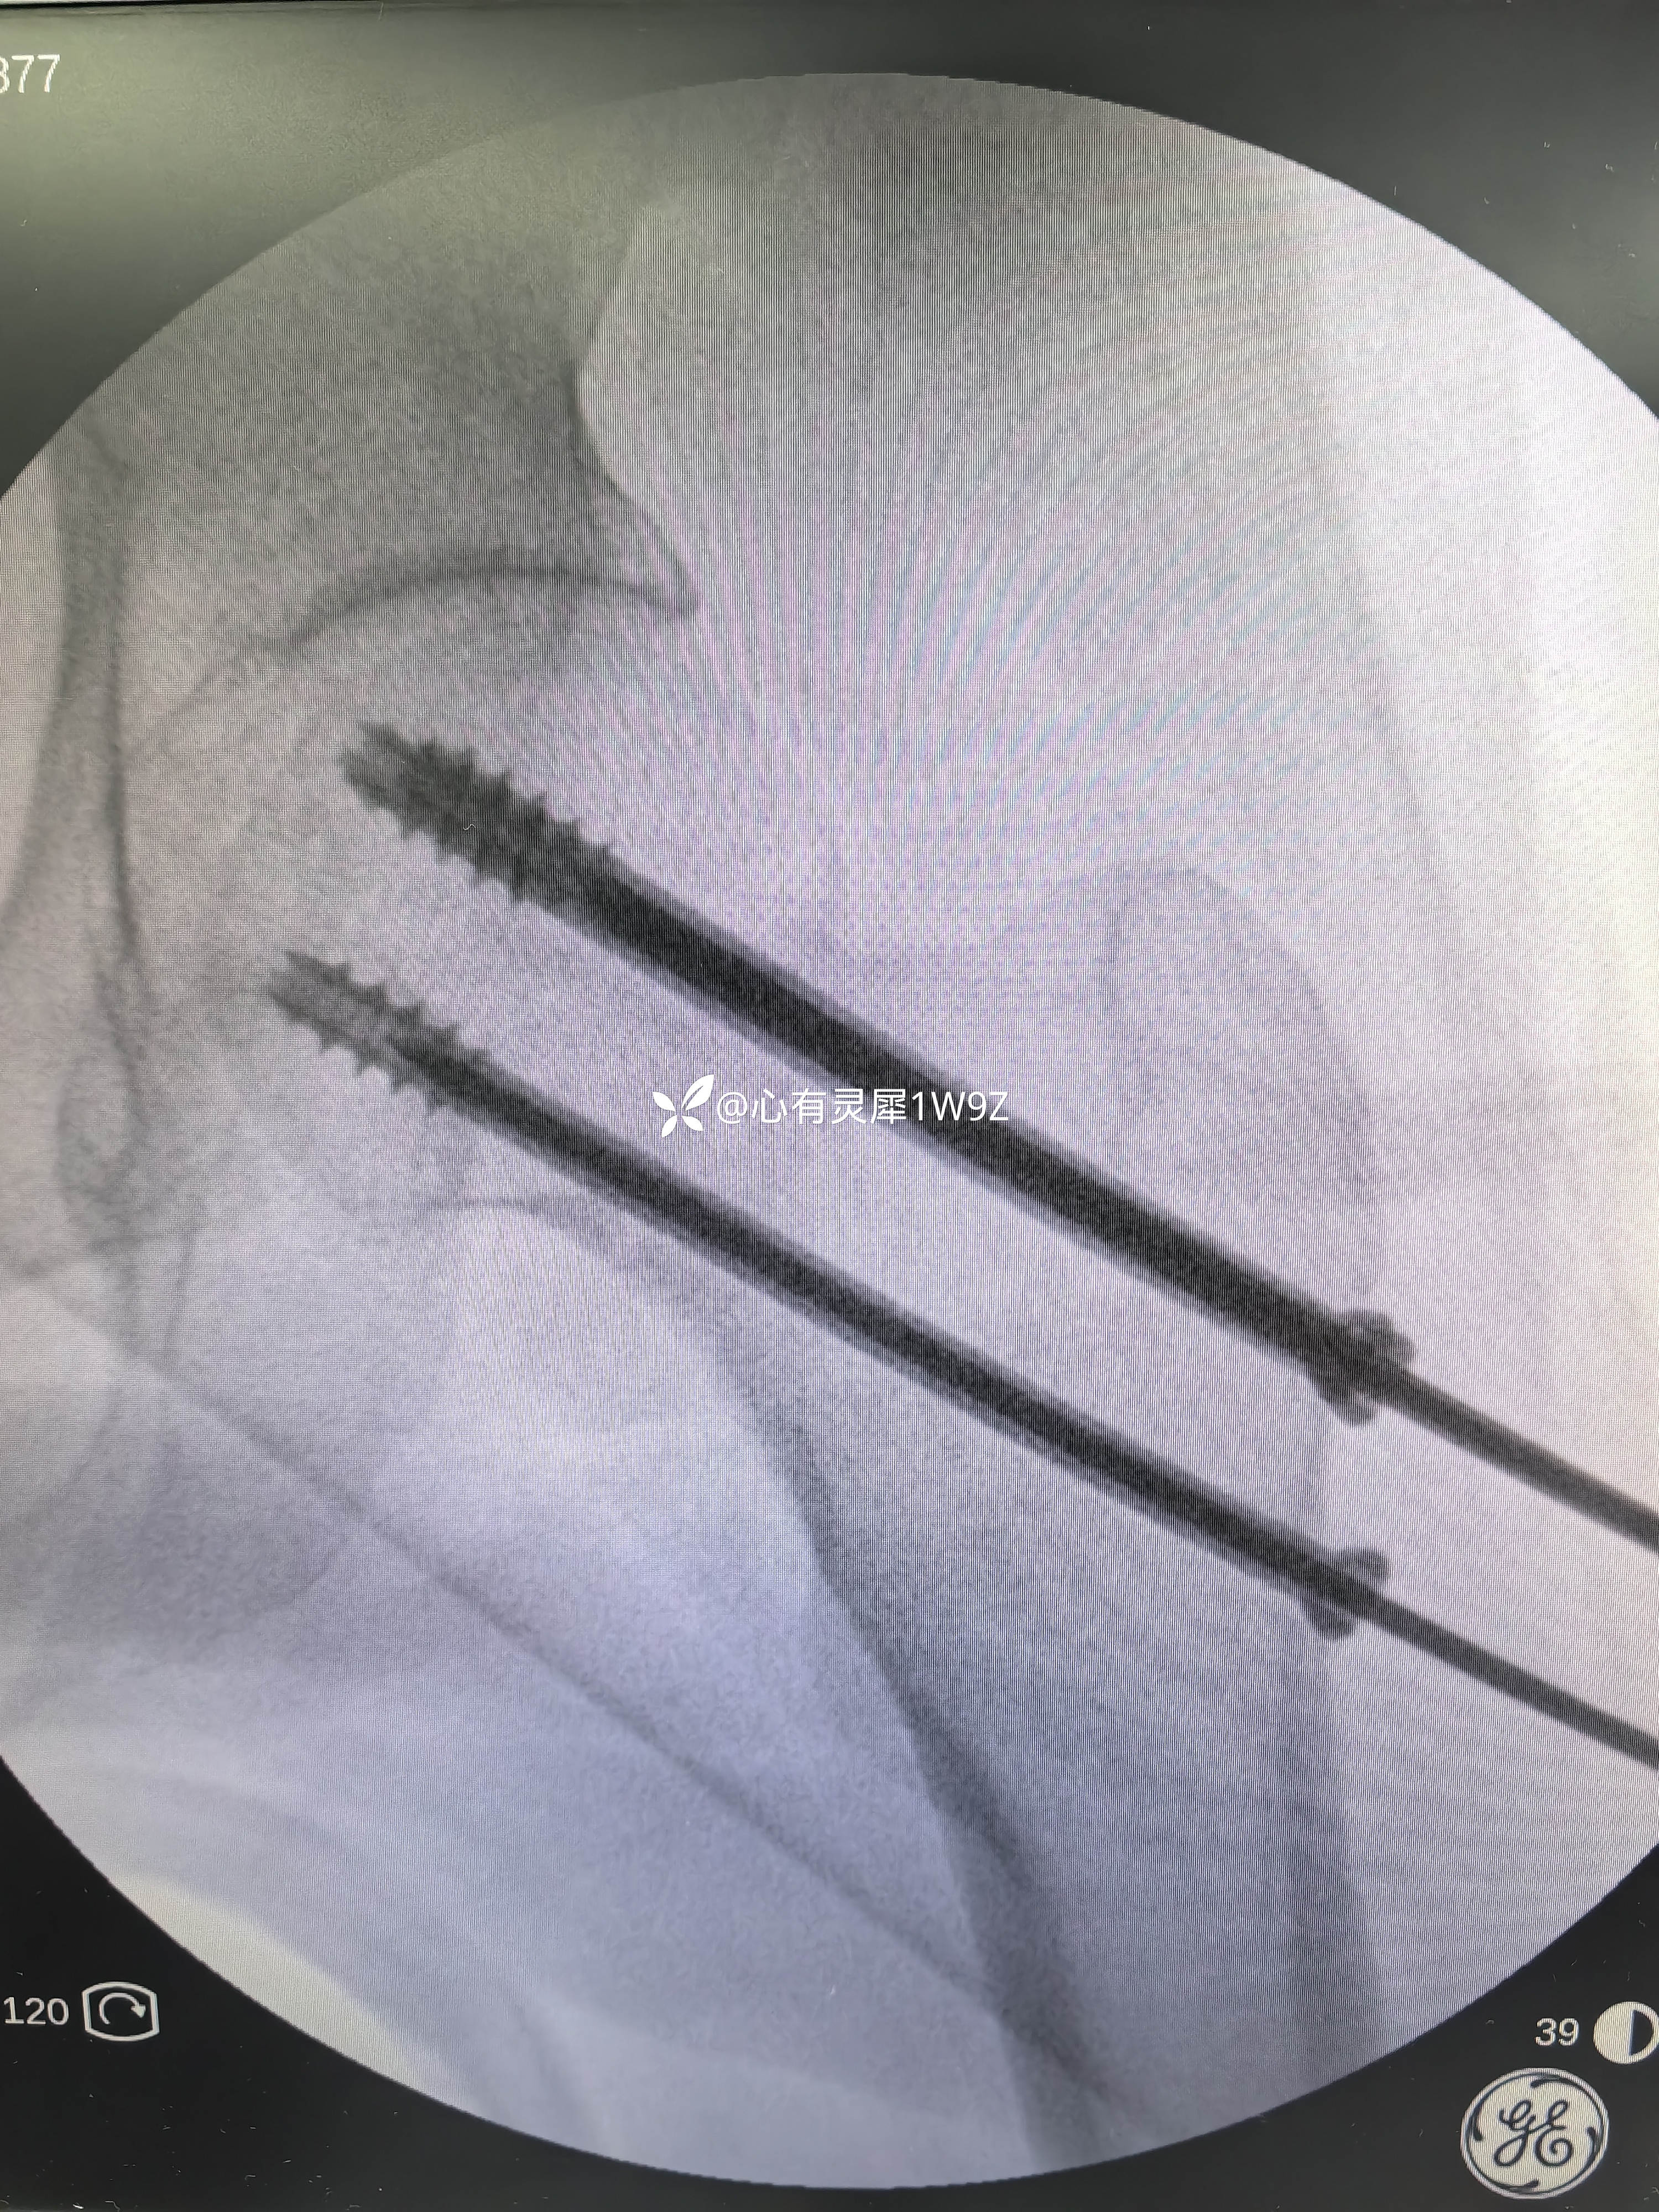

向患者及家属讲解治疗方案。患者和家属选择做内固定。积极准备后在24小时内手术。椎管麻醉,手术顺利,计划首先闭合复位,复位失败就切开复位,三枚加压空心钉固定。

2,关于贴壁,平行,长度,角度。自己感觉这次平行和长度都比较满意,贴壁还可以,角度不是很完美,感觉可以接受,就没有再调整。